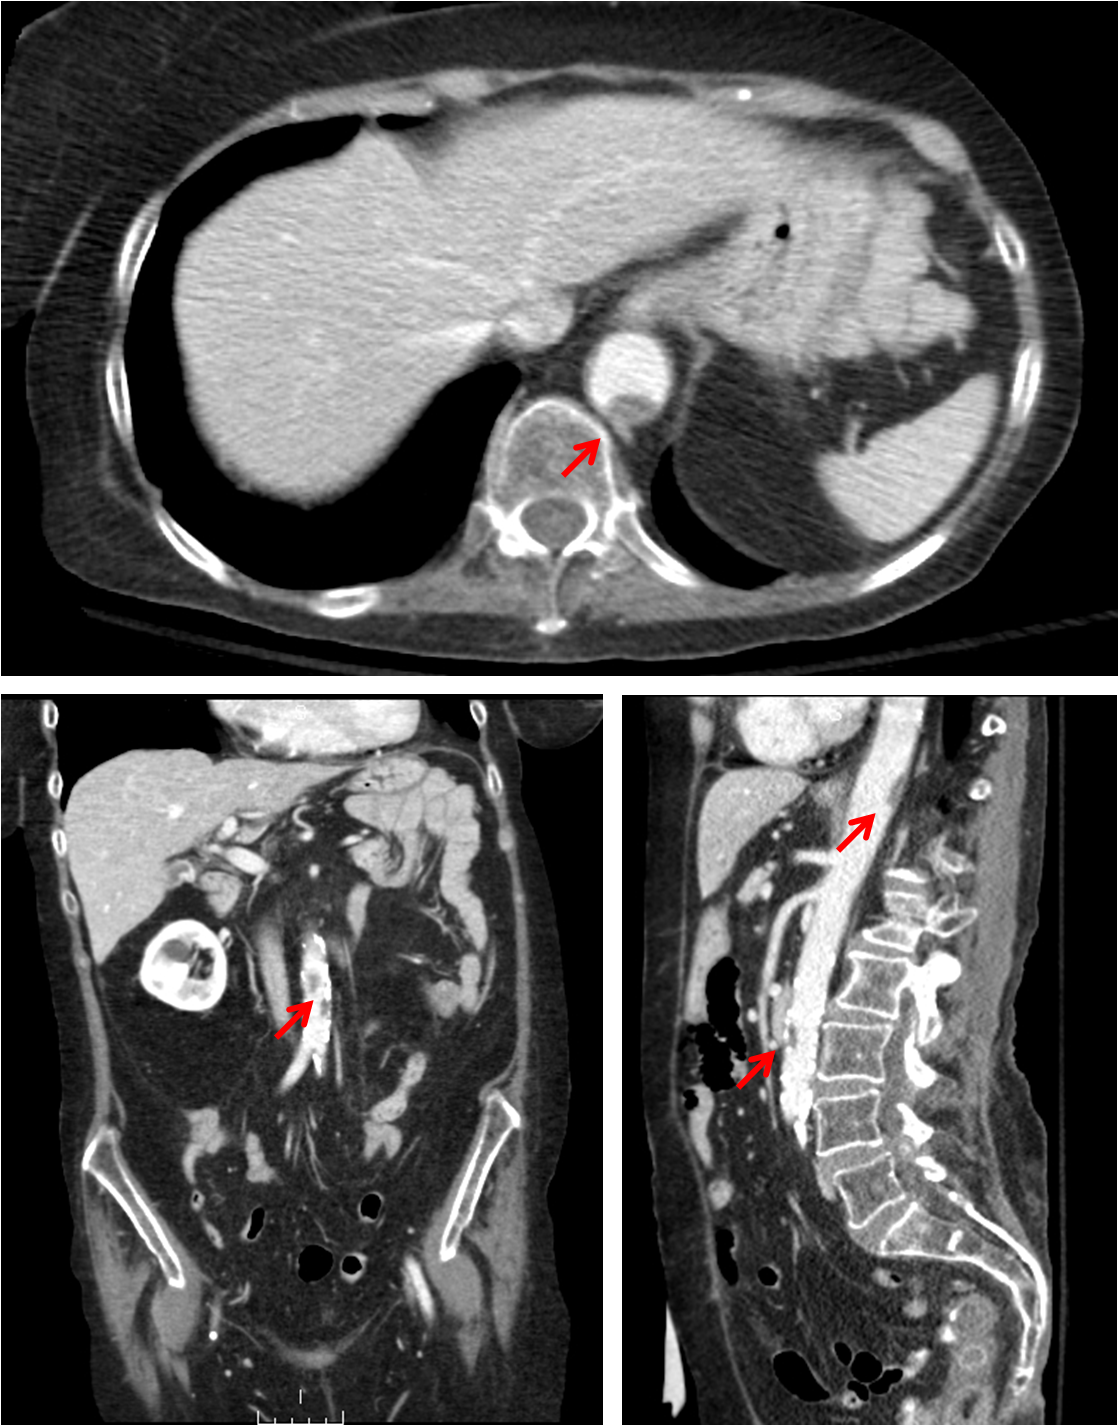

Mural thrombus

Computed tomography showing mural thrombus in the aorta (marked by the red arrows)